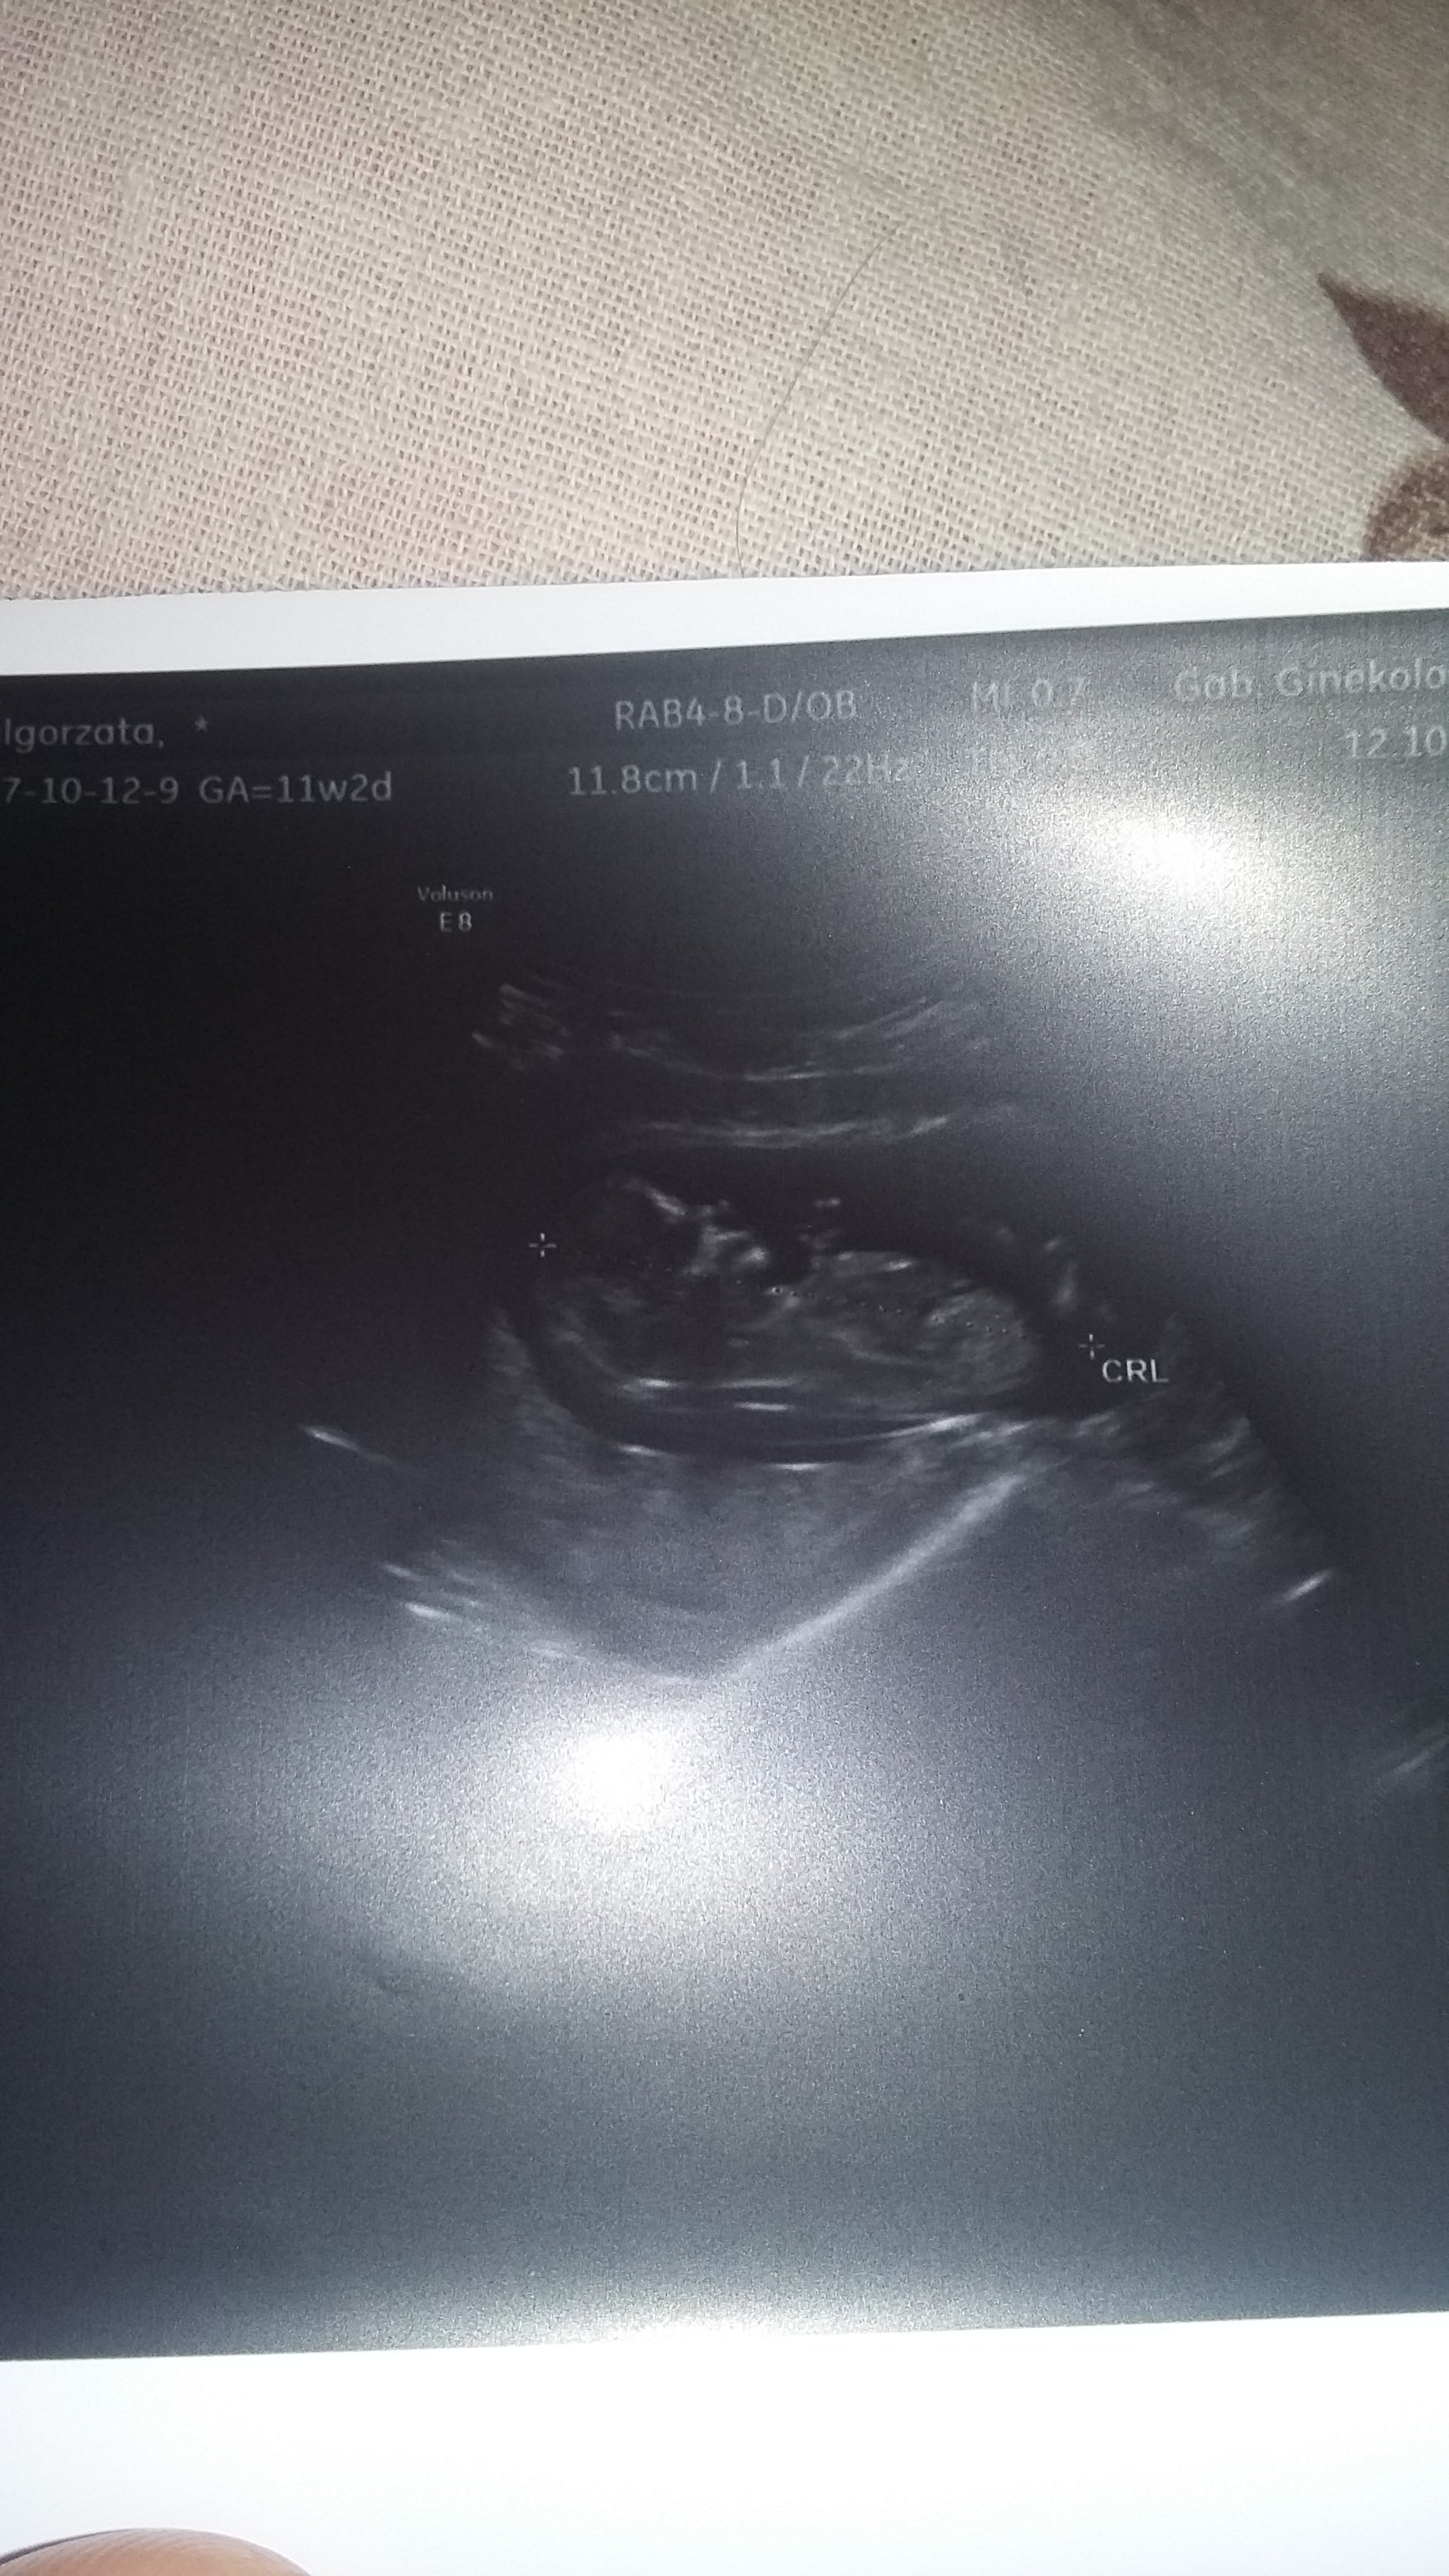

CudownieHej kochane ja juz po prenatalnych pisze dopiero teraz bo bylam na zakupach i nie dawno wrocilam. U nas wszystko w porzadku malenstwo ma prawie 6cm przeziernosc karkowa czyli NT 1.7 serduszko wporzadku 163 udzerzen na minuteTylko nie powiedzial mi jeszcze jaka plec bo jest jeszcze za male troche